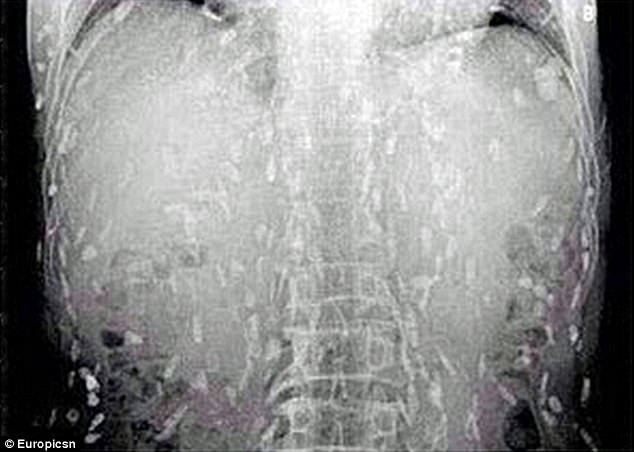

2017年07月17日前幾天,廣東一名男子腹痛難忍,皮膚搔癢,去當地的醫院求診。醫生為他拍X光片檢查,結果在X光片上看到了密密麻麻的白色斑點。大家倒吸一口冷氣,最後才確定,這些全都是絛蟲!

▼那名男子表示,自己平時愛吃生魚片,沒想到竟然會因此感染絛蟲。為他治療的醫生稱,很多人誤食含有絛蟲蟲卵的食物染病,如果治療不及時,會發展成囊蟲病。類似的病人,近年來醫院已經接診過好幾例,他們都有一個共同點,那就是愛吃生魚片。